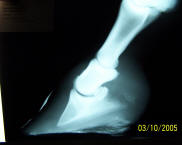

These are

tough radiographs to see, but this is a beautiful case, so I put them

up, anyway. the attending vet diagnosed a 14 degree rotation and full

I just

now had the follow-up radiographs taken, after four years of total

comfort. This horse is very comfortably ridden 3-4 times a week, and is

as happy as a horse can get. |

Another grazing muzzle, a few

less trips to the feed store, routine natural hoof care and another

wonderful horse snatched from the edge of the grave!!! This is really

fun!